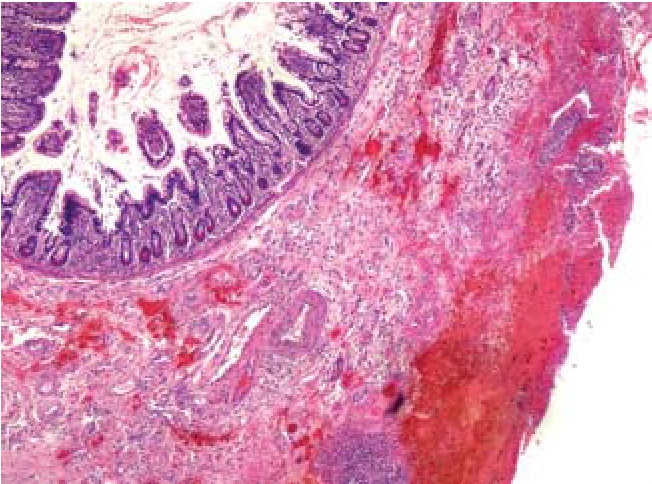

Наиболее характерным для острых перфоративных язв тонкой кишки было первичное повреждение слизистого слоя с развитием множественных некрозов эпителия (рис. 4, 8) на фоне массивной нейтрофильной инфильтрации (рис. 4–8) и значимых гемоциркуляторных расстройств в виде резкого полнокровия и тромбозов сосудов, а также геморрагического пропитывания как слизистого, так и подслизистого слоев (рис. 5, 7, 8), массивного разрастания в подслизистой основе грануляционной ткани (рис. 6) с исходом в фиброз и липоматоз (рис. 8).

Рис. 7. Края язвы: некрозы слизистой оболочки, геморрагическое пропитывание подслизистого слоя, полнокровие сосудов, нейтрофильная инфильтрация. Окраска гематоксилин – эозином, ув. ×40